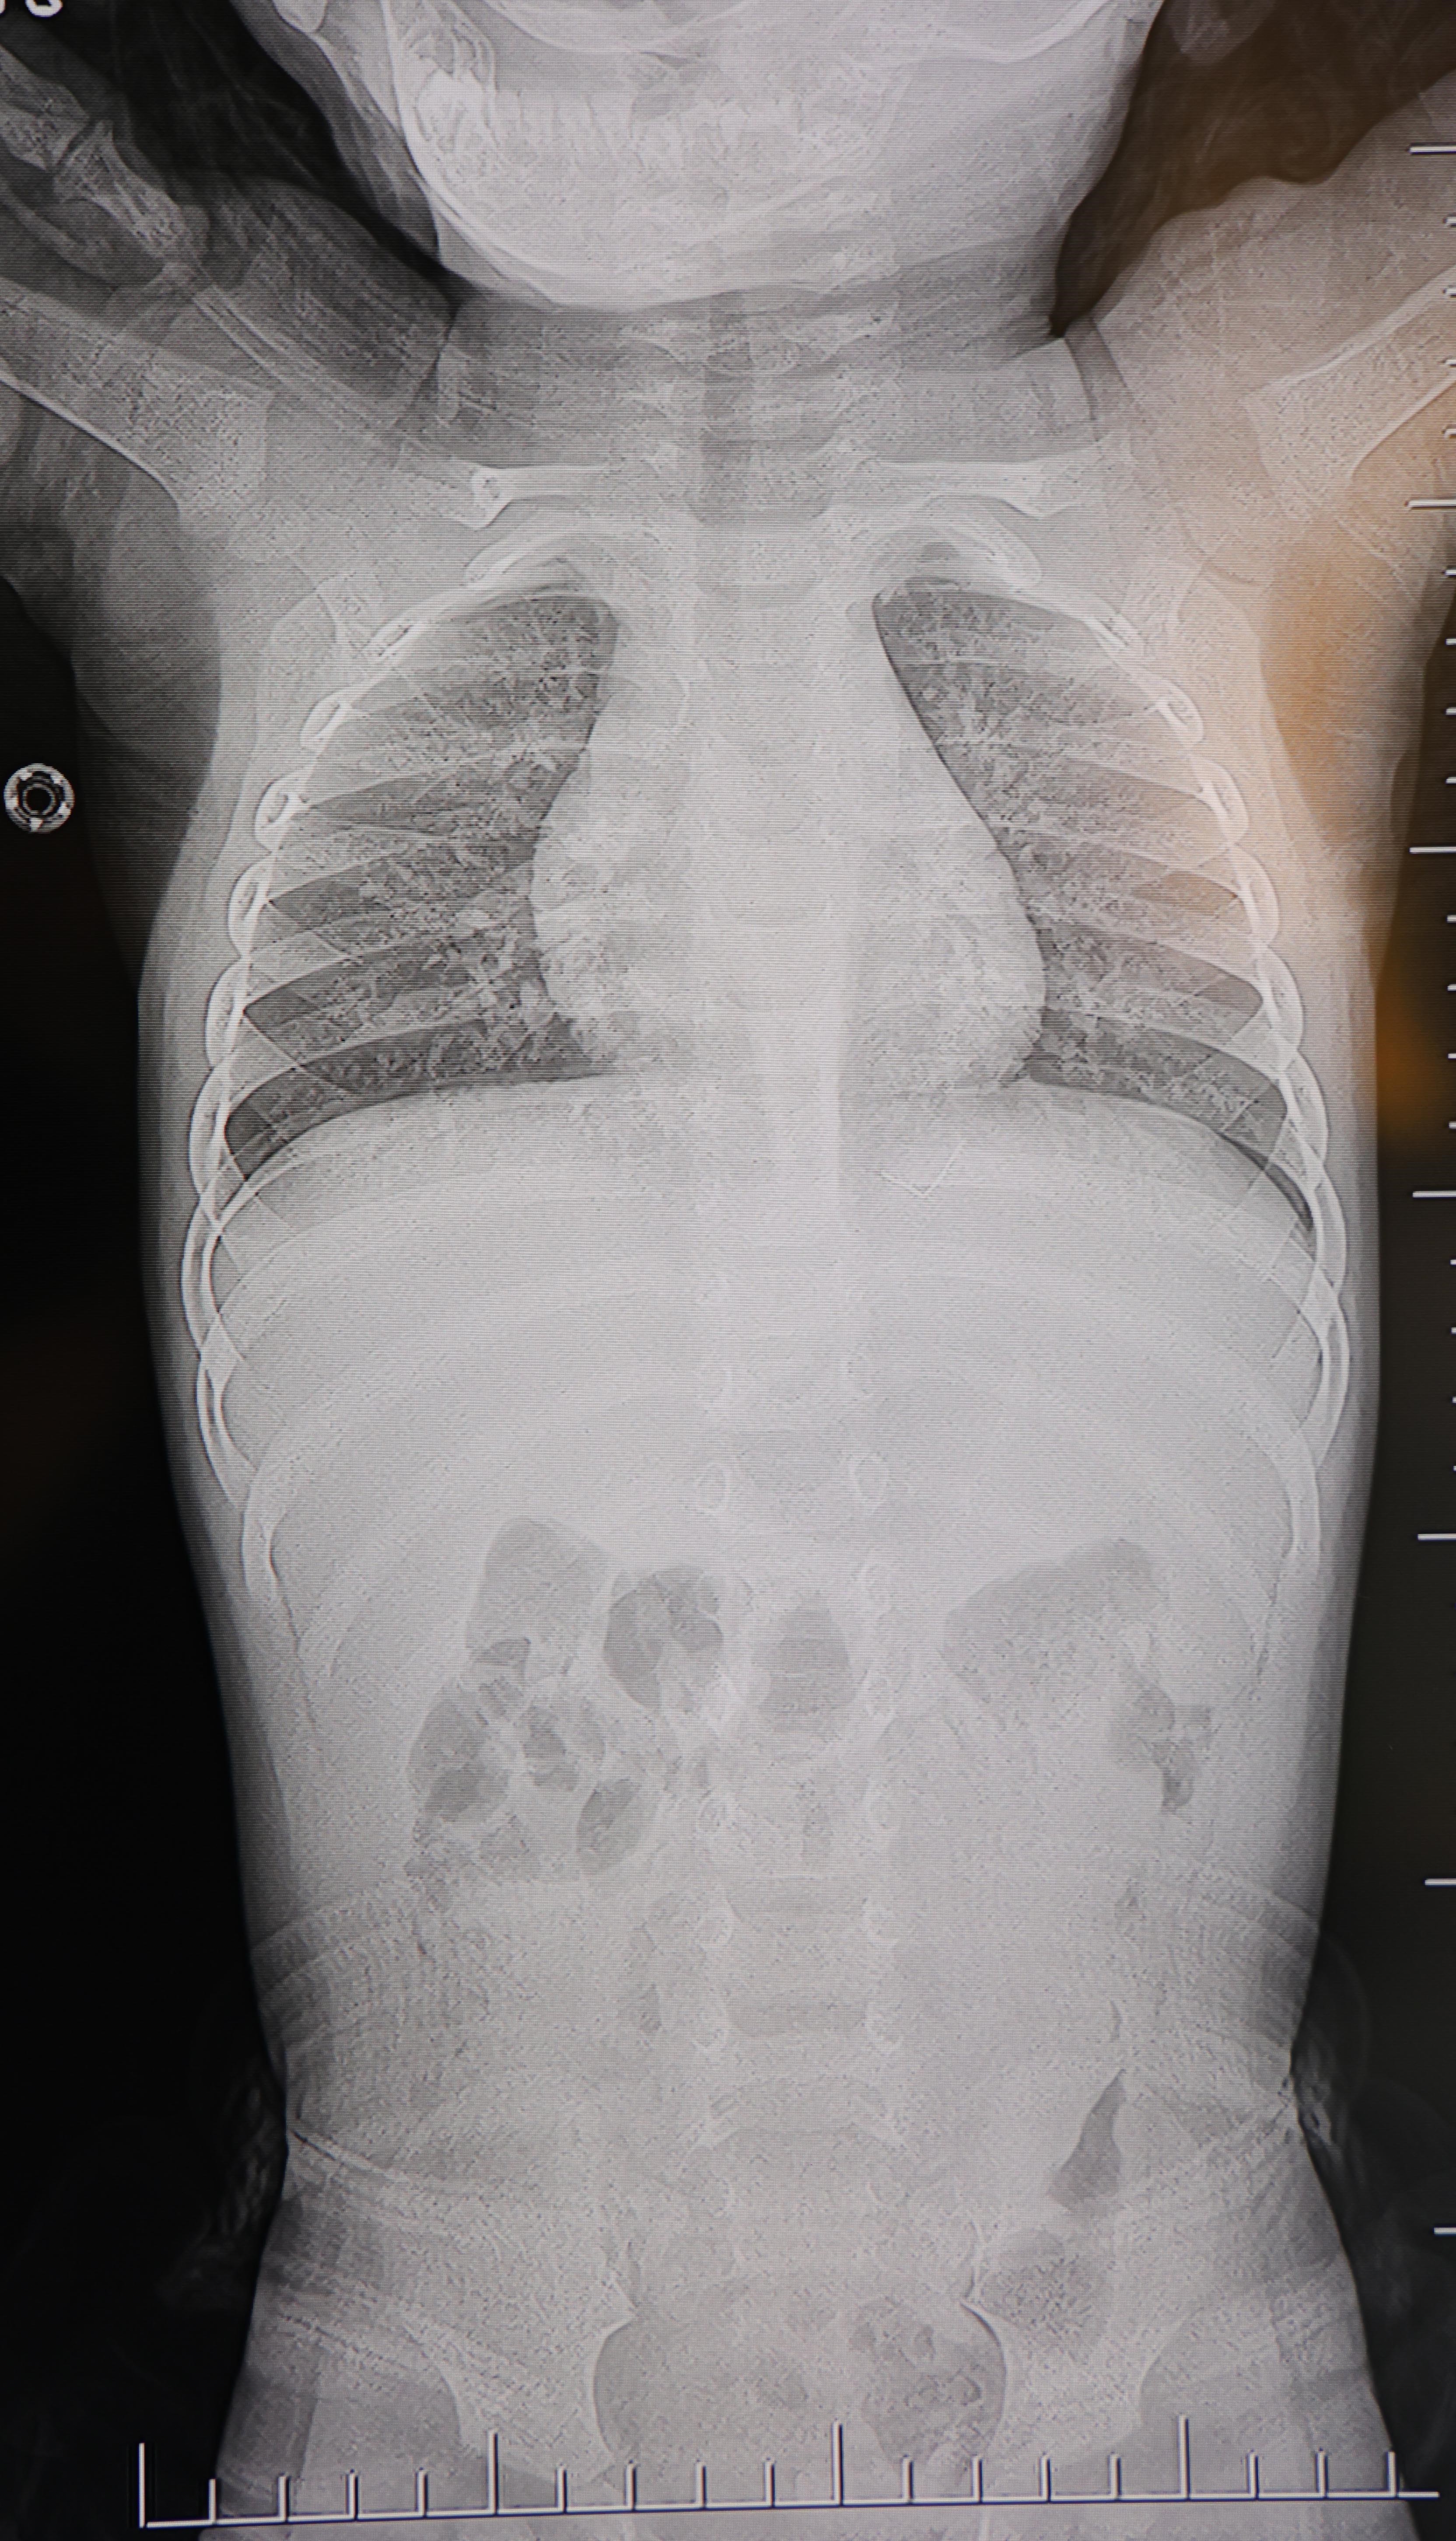

Alınan bilgiye göre, Kahramanmaraş'ta farklı ortopedi, çocuk cerrahisi ve beyin cerrahisi kliniklerine başvurusu yapılan bir yaşındaki bebeğin, sırt bölgesinde yabancı bir cisim olduğu ancak müdahalenin zor olduğu ve 8 yaşına kadar beklenmesi gerektiği bildirildi. Aile, bebekleri için son olarak HG Hospital'e başvurdu. HG Hospital Beyin ve Sinir Cerrahisi Uzmanı Prof. Dr. İdris Altun tarafından yapılan tetkiklerde, yabancı cismin cilt altında, omurilik kanalına yakın bir bölgede olduğu ve akciğer zarına doğru ilerlediği belirlendi. Hasta, genel anesteziye alınmadan, lokal anestezi ve sedasyon eşliğinde ameliyata alındı. Yapılan müdahalede yabancı cisim tamamen çıkarıldı. Çıkarılan cismin, ince zımba teline benzer metal bir tel olduğu ve yaklaşık 2 santimetre uzunluğunda bulunduğu tespit edildi. Hasta, aynı gün taburcu edildi.

Konuya ilişkin açıklama yapan Prof. Dr. İdris Altun, "Sırtında yabancı bir cisim olduğu söylenmiş ancak çıkarılamayacağı ve 8 yaşına kadar beklenmesi gerektiği ifade edilmişti. Bize başvurduğunda yaptığımız tetkiklerde, cilt altında, omurilik kanalına çok yakın ve akciğer zarına doğru ilerleyen bir yabancı cisim tespit ettik. Hastamızı tamamen uyutmadan, lokal anestezi ve sedasyon eşliğinde müdahale ederek lezyonu tamamen çıkardık. Çıkardığımız cismin ince zımba teline benzer, yaklaşık 2 santimetre uzunluğunda metal bir tel olduğunu gördük. Bu yabancı cisim alınmasaydı, bölgede enfeksiyon gelişebilirdi. Enfeksiyon sonucu omurilik kanalında ciddi hasarlar oluşabilir, çocuk büyüdükçe cismin hareket etmesine bağlı olarak omurilikte zedelenmeler meydana gelebilirdi. Ayrıca yana doğru ilerleyerek akciğer zarına ve akciğere batma riski vardı. Bu da enfeksiyona ve ilerleyen süreçte tümörle karışabilecek tablolara neden olabilirdi. Şu an hastamız gayet sağlıklı. Gerekli kontrolleri yaptık ve aynı gün taburcu ettik" dedi.